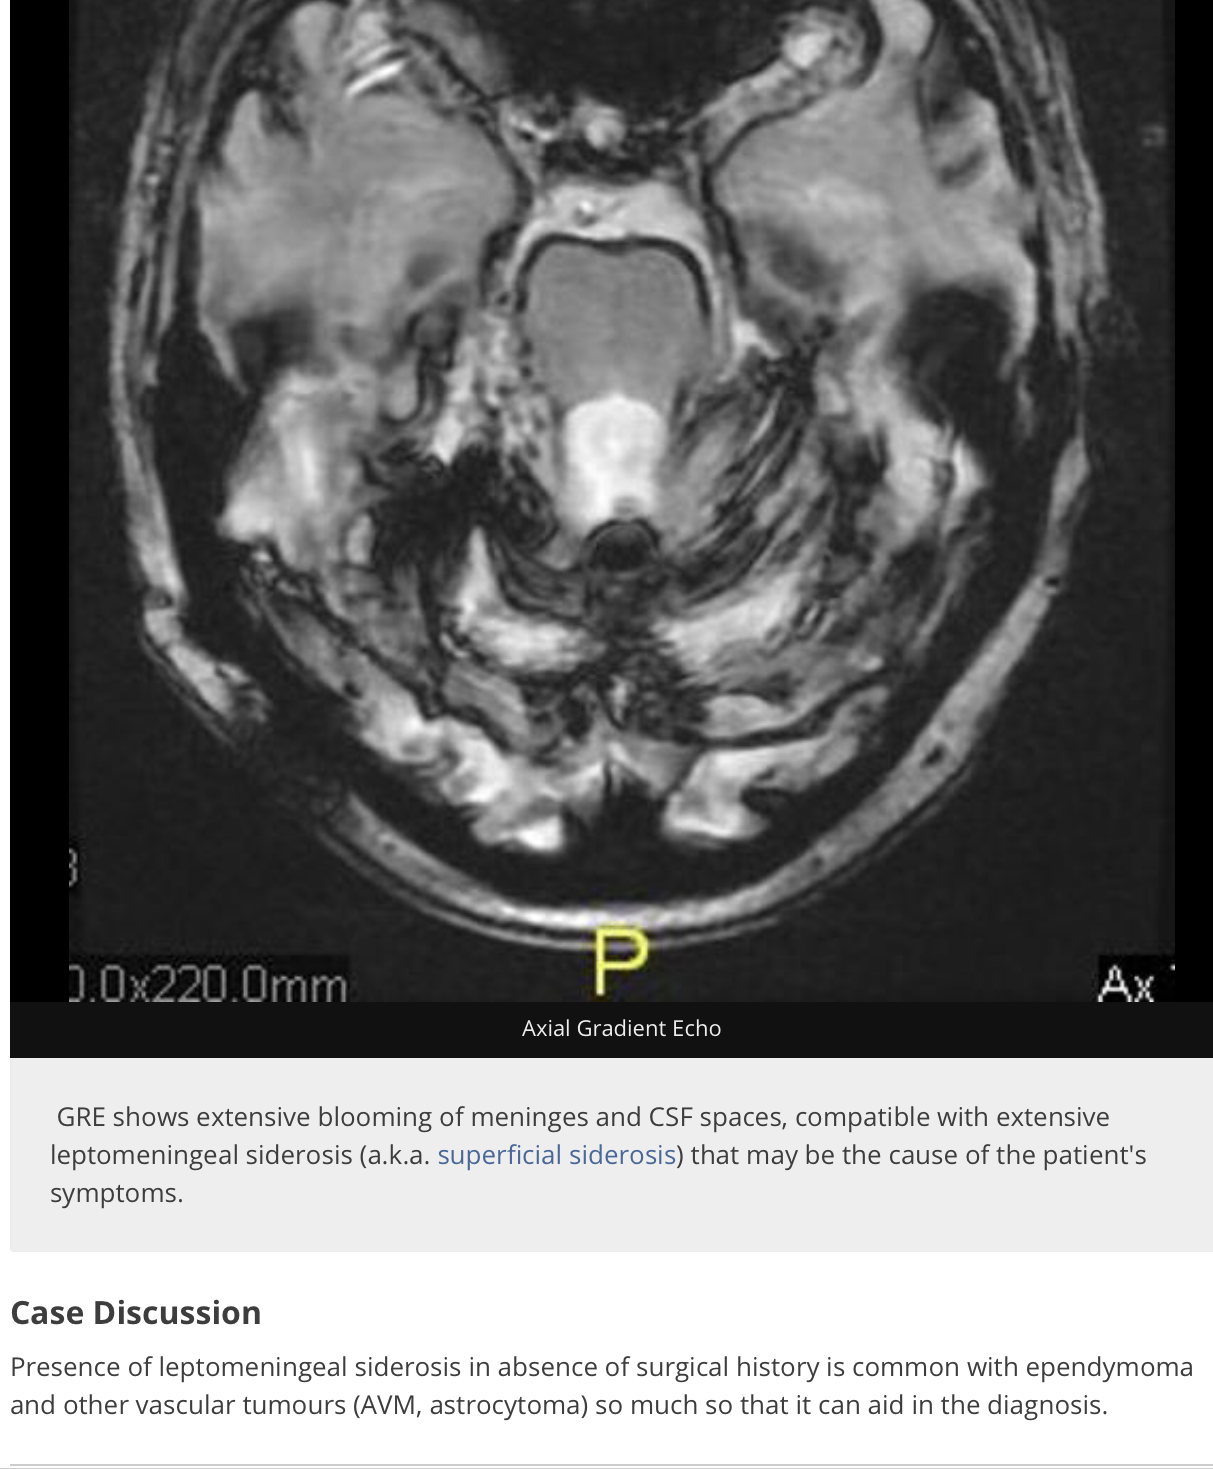

SUPERFICIAL SIDEROSIS - what is it?

SIDEROSIS

(symptoms: vertigo, tinnitus)